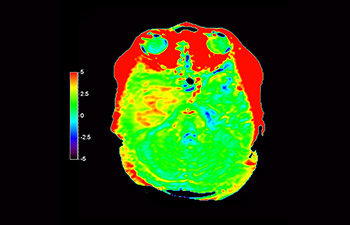

Chemical exchange saturation transfer(CEST)imagingは、MRIにおける分子イメージングの手法であり、その代表的なものにamide protontransfer(APT)imagingがある。MRIはプロトン密度と緩和時間に基づいた画像コントラストを得るのに対し、APT imagingでは可動性タンパク中のペプチド(アミド基)の濃度と交換速度に基づくコントラストが得られ、脳腫瘍の悪性度判定や放射線壊死と脳腫瘍再発との鑑別などに応用されている¹,²。

APTwイメージングでは、アミド基(NH)が対象となる。生体内のアミド基は、主にタンパク質やペプチドに含まれており、平均的には +3.5ppmの周波数に分布するとされる。アミド基のプロトンはバルク水から +3.5ppm離れた周波数帯に存在するため、交換プロトンの信号を抑制させる飽和パルスを +3.5ppmで選択的に照射する。飽和パルスによって信号が抑制されたアミド基のプロトンは、バルク水へ順次移動し、バルク水の信号を低下させる。飽和パルスの周波数を変化させながらバルク水の信号抑制を観察することで、間接的にアミド基を観察することができる(図1)。

CESTは、ごくわずかな共鳴周波数差(数100Hz)にあるプロトンを選択的に飽和させて画像化するため、静磁場B0(数十MHz)のわずかなズレでも、結果に大きな誤差が生じる。APTwイメージングでは、3D DIXON TSEシーケンスを用いB0補正を行っている。本シークエンスの利点は、3 point Dixonによる高精度のB0補正と撮像を一体化させB0不均一性に強い点と、スライスギャップなく3Dで広範囲の撮像が可能となった点である。これにより、B0不均一性に強く安定して広範囲のAPT強調像を撮像することができる⁴。